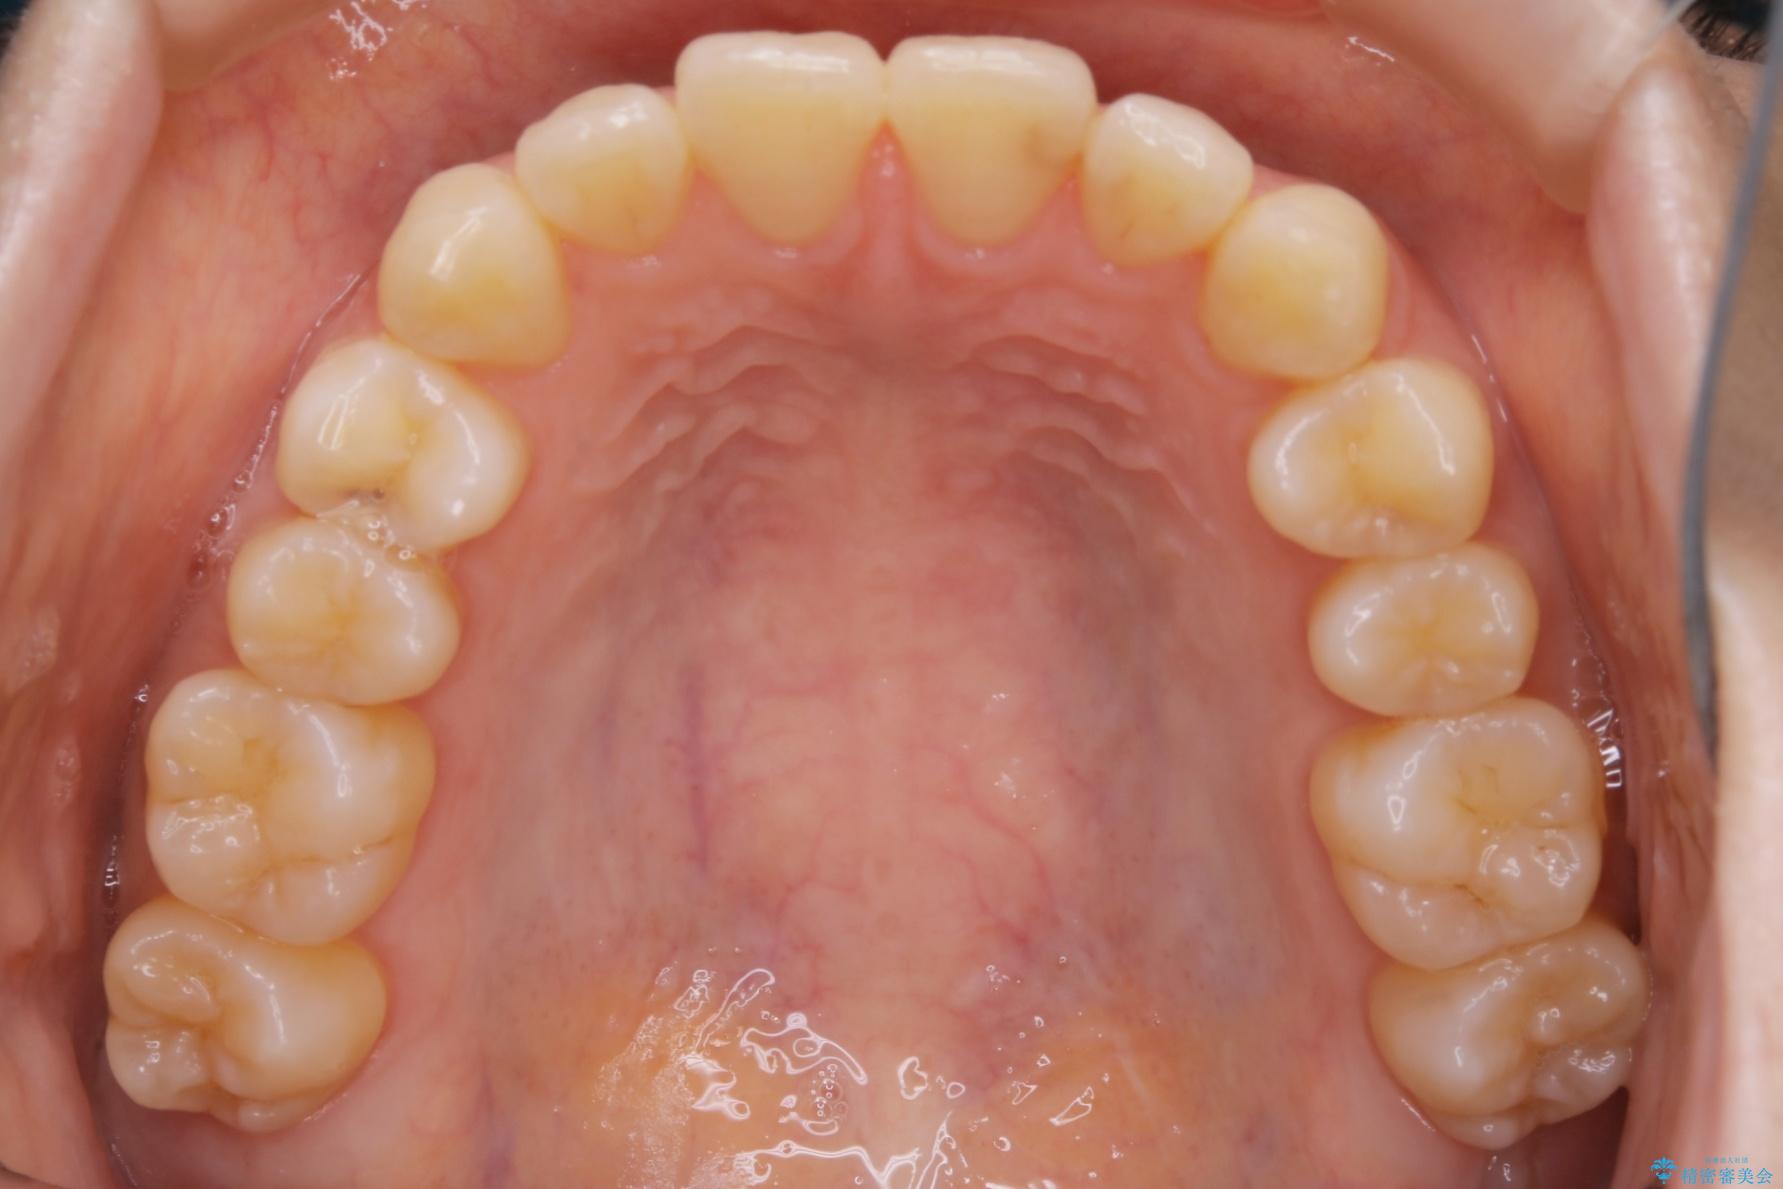

下の前歯のガタつきが気になるとご来院された患者様です。

インビザラインのライトパッケージにて、歯列拡大とディスキング(IPR)をを行いスペースをつくり非抜歯で治療を行いました。

歯列弓の拡大

歯並びが悪くなる原因の一つに「歯列弓の狭窄」というものがあります。

奥歯や前歯が内側(舌側)に倒れ込んでしまったり、歯が生えてくる位置が内側になってしまうことにより歯並びのアーチが狭くなってしまうことを言います。

このような場合、歯並びのアーチを拡大してあげるだけでもガタつきを無くすためのスペースがかなり作れることがあります。